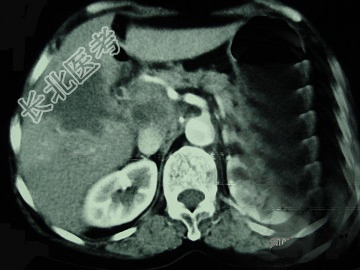

- 单项选择题女,65岁, 右季肋区疼痛二个月,CT扫描所见如图, 最可能的诊断为( )